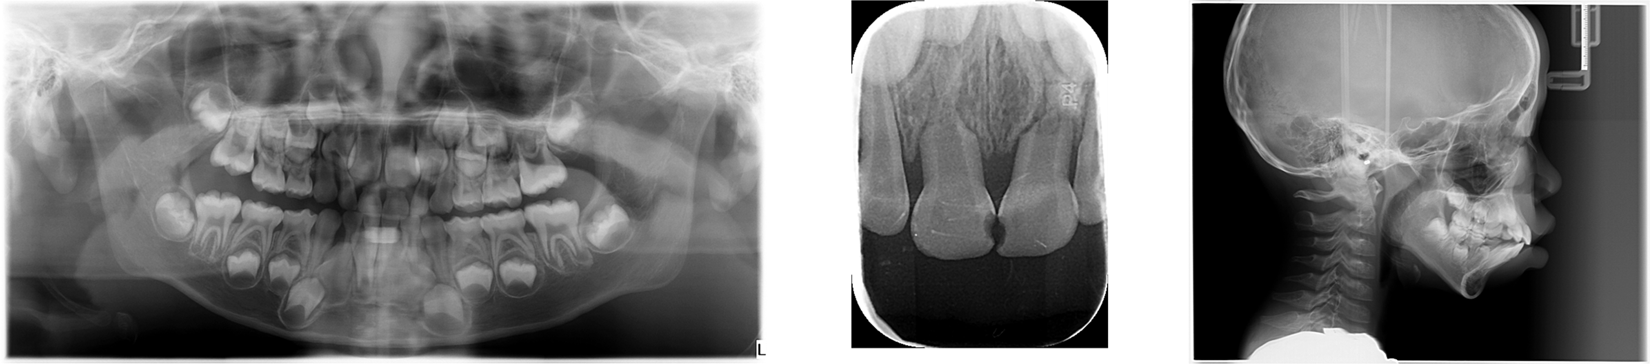

Fig. 5

From: Children’s dental panoramic radiographs dataset for caries segmentation and dental disease detection

The figure shows three types of dental images we collected from hospitals, all of which are important tools for dentists to diagnose dental diseases. From left to right: dental panoramic radiographs, intraoral scan, CBCT.